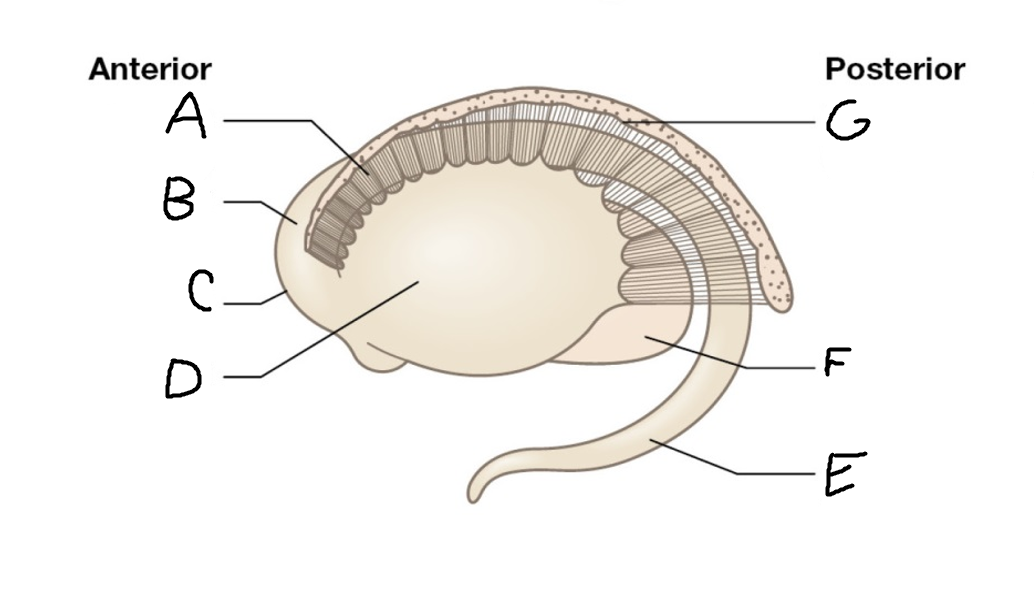

B

anterior horn of lateral ventricle

C

head of caudate nucleus

D

internal capsule (anterior limb)

E

putamen

F

globus pallidus

G

Thalamus

H

External capsule

I

internal capsule (posterior limb)

J

tail of caudate nucleus